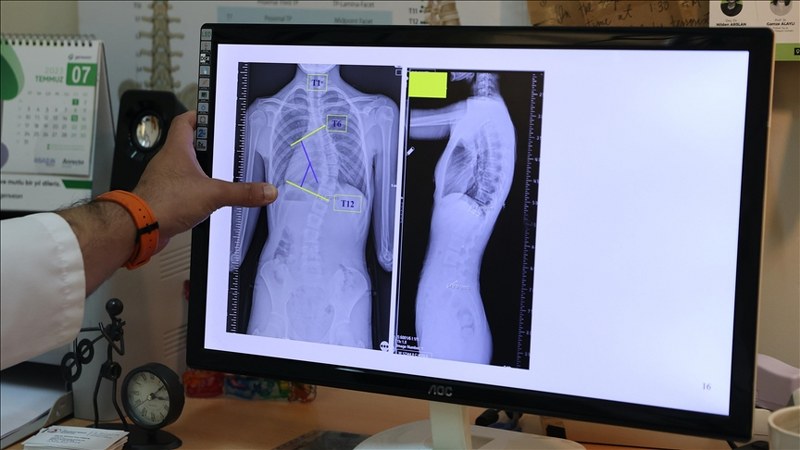

Başaran, yaptığı yazılı açıklamada, skolyozun omurganın üç boyutlu düzlemde sağa ya da sola eğrilmesi anlamına geldiğini, omurgada S veya C şeklindeki bu eğilmelerin yüzde 80’inin nedeninin bilinmediğini aktardı.

“Toplumda 10 dereceye kadar olan omurga eğriliklerine çok sık rastlıyoruz. Bunları normal, postürel eğrilikler olarak tanımlıyoruz. 10 dereceyi geçen eğriliklerde skolyoz hastalığı tanısı koyuyoruz. 20 dereceye kadar olan eğrilikleri 6 aylık aralıklarla büyüme dönemlerine göre takip ediyoruz. 20 dereceyi geçen eğriliklerde ise çocukları egzersiz programına alıyoruz ya da çeşitli korselerle hastalığının ilerlemesini engellemeye çalışıyoruz.”